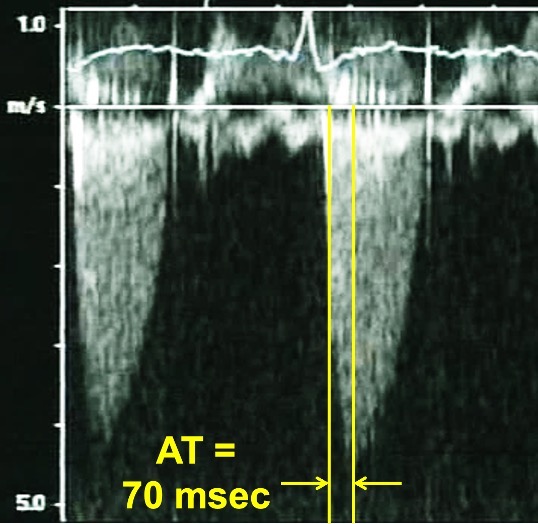

Progressive stenosis will lead to a prolonged acceleration time (AT), which is the time to the peak of the jet velocity as a result of delayed peaking of the velocity during systole. Therefore, the Doppler profile contour of an aortic prosthesis with stenosis with thrombi or pannus formation will be blunted and rounded as opposed to the triangular shape characteristic of a normally functioning prothesis (Figs. 4,5). This can be quantified by the ratio of the AT to the total ejection time (ET) over which blood flow occurs during systole, as a normal AT/ET ratio is less than 0.32. The AT as well as the AT/ET can also help distinguish true prosthetic obstruction from other conditions that confer a “functional” obstruction such due to high flow states (which can result from anemia, thyrotoxicosis, AV fistulas, or significant aortic regurgitation), pressure recovery, or patient prosthesis mismatch that can also lead to an elevated mean aortic prosthetic gradient. A functional obstruction will present with a peak velocity greater than 3 m/s, but the AT will be less than 80 ms, and the AT/ET, though it may be mildly elevated will not typically be greater than 0.37 [50, 51].

Fig. 4.Continuous Wave Doppler of a normally functioning aortic prosthesis with functionally obstructive hemodynamics. Note the triangular contour of the Doppler jet with a rapid acceleration time (AT) of 70 msec.